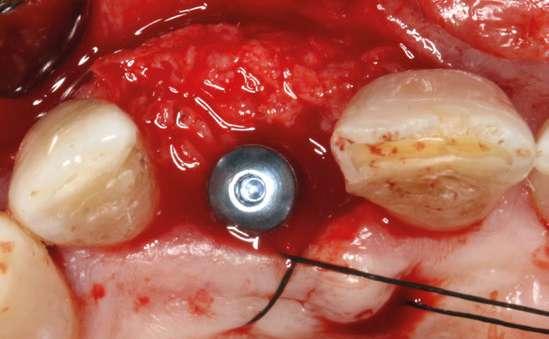

laterales se ponen de manifiesto aún más varias lesiones de esmalte que indican la parafunción en el paciente, unido a los desgastes excesivos en varias zonas (figuras 3 y 4). El paciente acude por dolor y movilidad en la pieza 11, que se ha incrementado en los últimos días, además de sensación de “diente crecido” que como podemos ver en las fotografías iniciales es real, ya que el diente se encuentra ligeramente extruido en relación con el contralateral. Estos signos parecen indicarnos una fractura o fisura. En la fotografía oclusal, podemos observar el desplazamiento del diente debido a la movilidad (figura 5). Posteriormente se realiza un sondaje positivo de la pieza, que lleva a 11 mm por lo que se confirma la sospecha de fractura y se procede a la exodoncia del diente, realizándose una regeneración posterior del alveolo con PRGF-Endoret y

esperándose 4 semanas hasta el cierre de los tejidos blandos y la neoformación ósea inicial para la colocación de un implante temprano. Cuatro semanas después, realizamos un cone-beam de control para conocer el estado del tejido óseo y poder planificar el implante. En el corte seccional observamos que se ha regenerado por completo el lecho receptor y tenemos un hueso óptimo para la inserción del implante, que por el tiempo transcurrido además es muy sencillo de expandir, con el propio implante generándose una expansión atraumática que nos permitirá ganar anchura ósea y con un implante estrecho de 3,5 mm de diámetro logramos posicionarlo sin dañar la desembocadura del nervio incisivo (figura 6). En cuanto a la longitud, con 7,5 es suficiente, no necesitándose un tamaño mayor para un correcto rendimiento biomecánico posterior.

Colocamos el implante generándose una ligera expansión vestibular, como mostramos en las imágenes intraoperatorias, para posteriormente ser sobrecorregido con hueso autólogo obtenido del fresado, embebido en PRGF-endoret y lograr una mayor anchura vestíbulo-lingual en la zona de colocación del im-

plante, clave para lograr una mejor estética y además un mantenimiento de los tejidos periimplantarios a largo plazo. En la fase quirúrgica colocamos además el transepitelial unitario para la realización de la carga inmediata y la colcación de un provisional atornillado horas después de la cirugía (figuras 7-14).

Figuras 7 y 8. Perforación inicial y colocación del implante expandiendo la zona vestibular.

Figuras 9 y 10. Visión vestibular tras la inserción del implante y colocación del transepitelial unitario para comenzar la carga inmediata.

Figuras 11 y 12. Sobre-corrección vestibular y cierre primario de los tejidos con un monofilamento no reabsorbible alrededor de la tapa de protección del transepitelial.